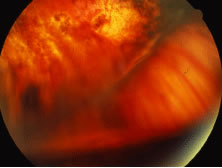

A variable number of eyes, up to 75%, develop retinal detachments (Fig. 5). Prophylactic laser for demarcating the areas of active retinitis from normal retina has been advocated to create chorioretinal adhesions that prevent retinal detachments around sites of retinal break formation (which usually occur at the zone between affected and healthy retina). Han and associates43 reported five cases treated with prophylactic laserpexy in addition to antiviral, steroid, and antiplatelet therapy. After 15 months of follow-up, no retinal detachments were noted. Sternberg and coworkers44 described a 75% decrease in the rate of retinal detachment using prophylactic photocoagulation. Some have advocated the creation of a “new ora serrata” by applying confluent rows of laser burns posterior to the areas of retinitis. However, if traction forces from vitreous organization, epiretinal membrane (ERM) formation, or proliferative vitreoretinopathy develop as they commonly do, the contractile forces will be able to overcome any increased chorioretinal adhesion created by the laserpexy. However, McDonald and associates45 reported failure of prophylactic peripheral laserpexy to prevent retinal detachment in ARN patients. In addition, many cases of ARN result in a severe vitritis, limiting the view for a planned laserpexy (Fig. 6). Therefore, vitrectomy with endolaser and concomitant encircling of the eye with a scleral buckle to reduce traction may be required in some patients.46,47 Decisions relating to the need for scleral buckling to support retinal breaks and the use of silicone oil or long-acting gases to repair retinal detachments should be made by an experienced vitreoretinal surgeon.40,48 Selection of cases to undergo operation should be made with consideration given to optic nerve function, visual potential, and medical control of retinitis.

Fig. 6. Failure of prophylactic laser treatment to stop the progression of a retinal detachment associated with retinal necrosis resulting from viral retinitis with progression of the detachment beyond the line of laser demarcation.